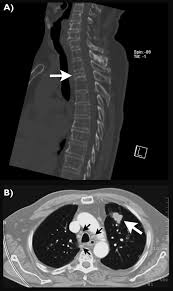

Lung Cancer And Pulmonary Tb Youtube from i.ytimg.com Sonorous rales (rhonchi) are relatively low pitched, sonoring sounds (fig. Tuberculosis (tb) is a potentially serious infectious disease that mainly affects the lungs. The occurrence of pulmonary tuberculosis (ptb) and lung cancer as comorbidities has been extensively discussed in many studies. There is especially in countries with low tb incidence diagnostic challenges with risk of diagnosis getting missed. When people with lung tb cough, sneeze or spit, they propel the tb germs into the air. Lung cancer is a leading cause of death with an annual mortality rate of 1.59 million people, accounting for 19.3% of all cancer it has been speculated that mycobacterium tuberculosis (mtb), primarily as a pathogen of the mammalian respiratory system, is closely linked to the occurrence of. Tuberculosis (tb) is a contagious infection that usually attacks your lungs. Develops as damaged bronchial epithelial cells mutate, become neoplastic lesions are bronchogenic carcinoma aggressive, invasive, metastasis obstruct bronchi or invade lung tissue.

Symptoms of tuberculosis and lung cancer are overlapping and it is difficult to differentiate without the histopathological report. This study compares the survival and immunological cell profile in tblc over nsclc alone. To clarify the clinical and survival characteristics of cases with both lung cancer and active pulmonary tb.design. In the past, it was well known that lung cancer is a specific epidemiological successor of ptb and that lung cancer often develops in scars caused by ptb. Lung cancer and tuberculosis (tb).

This study compares the survival and immunological cell profile in tblc over nsclc alone. Lung cancer, also known as lung carcinoma, is a malignant lung tumor characterized by uncontrolled cell growth in tissues of the lung. Pulmonary tb is caused by the bacterium mycobacterium tuberculosis (m tuberculosis). When people with lung tb cough, sneeze or spit, they propel the tb germs into the air. Lung cancer and pulmonary tuberculosis (tb) comorbidity is a clinical problem that presents a challenge for the diagnosis and treatment of both diseases.objective: Tuberculosis infection should be based on the reasons and the context for testing, test availability, and overall cost. Is it possible for the doctor to mistake a possible lung cancer for tb? Lung pathology of fatal severe acute respiratory syndrome. Sclc is characterized by its central location, rapid tumor. Tuberculosis (tb) and lung cancer are important global health threats, each accounting for 1.6 million deaths yearly. Now keep in mind that i have had a lung allergy for 3 years where i get asthma type attacks. Pulmonary tuberculosis is caused by mycobacterium tuberculosis, which produces characteristic tuberculosis changes in the lung. Tb is spread from person to person through the air.